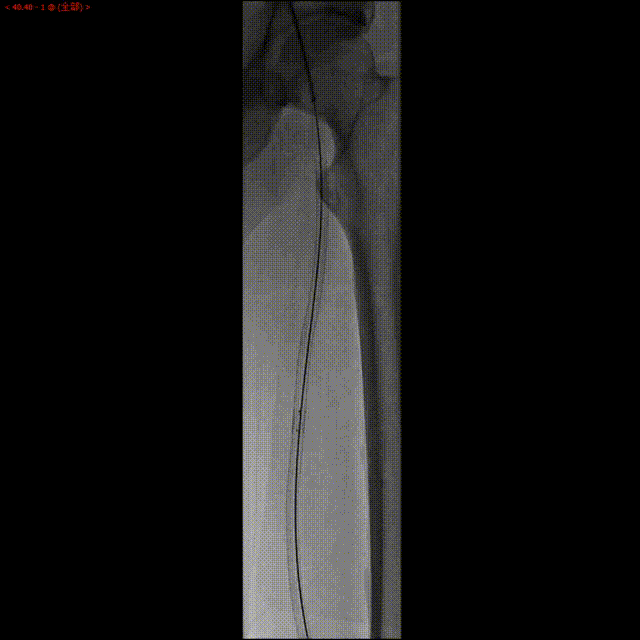

现病史:患者于4年前出现活动后双下肢疼痛。2018年5月下肢动脉造影示双侧股浅动脉慢行完全性闭塞,于右侧股浅动脉植入支架1枚,左股浅动脉植入支架2枚,2019年5月造影示左股浅动脉支架内闭塞,行球囊扩张术复通。2021年12月下肢彩超示双侧股浅动脉支架闭塞,右侧股浅动脉球囊扩张术后复通。

左侧股浅动脉支架内重度狭窄,支架出口闭塞,股深动脉侧支供应股浅动脉远段。

此患者为73岁老年男性,合并糖尿病,平时血糖控制不佳。股浅动脉支架植入术后,反复出现支架内再闭塞。此次左侧股浅动脉严重狭窄,支架内全程狭窄,远端支架出口闭塞,借侧支循环显影。